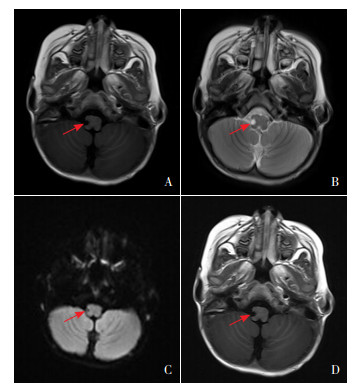

实验室检查:头部MRI示T1WI相延髓右侧背外侧低信号,T2WI相延髓右侧背外侧高信号,弥散加权成像上病变呈低信号,增强扫描病变无强化,呈低信号,提示软化灶(图 1)。头部CTA示头臂干、左侧颈总动脉及锁骨下动脉起源无异常;椎动脉左优势型,右侧椎动脉纤细,断续显示,右侧椎动脉V4段近端部分未显示,远端部分显影,考虑基底动脉盗血所致(图 2)。血常规、全血细胞形态、红细胞沉降率、肝肾功能、心肌酶、铜蓝蛋白、血氨、乳酸、血糖、甲状腺功能、狼疮全套、抗中性粒细胞胞浆抗体(ANCA)、凝血功能无异常。脑脊液常规及生化无异常,血清及脑脊液抗中枢神经系统水通道蛋白4(AQP4)抗体、抗髓鞘少突胶质细胞糖蛋白(MOG)抗体、免疫性脑炎相关抗体、寡克隆带均阴性。视频脑电图、双下肢肌电图、心脏彩超、腹部彩超、四肢动静脉彩超、颈椎+胸椎MRI平扫增强、头部MRA+MRV无异常。

图 1 头部MRI检查 图A为轴位T1WI相,延髓右侧背外侧见小片状长T1信号,界清,提示软化灶(箭头所示);图B为轴位T2WI相,延髓右侧背外侧见小片状长T2信号, 界清,提示软化灶(箭头所示);图C为弥散加权成像,病变呈低信号,提示软化灶(箭头所示);图D为增强扫描,病变无强化,提示软化灶(箭头所示)。 |

入当地医院后患儿病情进行性加重,给予肠内营养、头部亚低温、甘露醇降颅压、丙种球蛋白封闭抗体、低分子肝素钠改善局部循环,病情好转,但仍残留声音嘶哑、患侧共济失调、Horner综合征等表现,为求进一步治疗转入我院。入我院后头部MRI提示延髓右侧背外侧梗死后软化灶;头部CTA提示椎动脉左优势型。开始给予高压氧、局部神经肌肉电刺激、针灸、推拿对症治疗促进局部脑功能恢复。患儿声音嘶哑逐渐恢复,可与母亲正常交流,仅残留患侧共济失调、Horner综合征,嘱其规律于我院儿科门诊行功能康复治疗。患儿自发病起一直存在右侧球结膜充血症状。

3 诊断思维该患儿病例特点:(1)2岁幼儿期男童,急性起病。(2)以右侧眼睑下垂、运动倒退起病,同时伴有构音障碍,吞咽困难、饮水呛咳,哭闹时左眼有泪、右眼无泪,向右侧摔倒。(3)体检示右肩下垂,向左侧转头无力,左侧头部有汗,右侧头面部无汗,右侧眼球外展活动可,右侧眼睑下垂最严重时遮盖眼球5~7点位置,右侧结膜略充血,双侧瞳孔大小不等,左侧3 mm,右侧2 mm,对光反射存在,咽反射减弱,悬雍垂居中,右侧肢体肌力减弱4+级,活动较左侧欠灵活,右侧腹壁反射、提睾反射、膝腱、跟腱反射减弱。(4)出生史及发育史正常。(5)头部CTA示右侧椎动脉横突孔段较左侧明显纤细,考虑左侧优势型供血,右侧椎动脉入颅后未显影,双侧后交通动脉开放;头部MRI示延髓右侧背外侧梗死后软化灶。

4 诊断及确诊依据诊断:WS。诊断依据:(1)临床表现:①患儿有恶心呕吐、眼震等前庭神经核损害症状,②有构音障碍、吞咽困难等疑核及舌咽、迷走神经损害症状,③有病灶侧共济失调,④同侧Horner综合征;(2)辅助检查:头部MRI提示延髓右侧背外侧梗死后软化灶,头部CTA提示右侧椎动脉V4段近端部分未显影,引起延髓右侧背外侧缺血性梗死。

头部MRI、CTA技术的开展在中枢神经系统疾病的诊断中发挥重要作用。在WS患者中,头部MRI较CT诊断价值更高。孙庆华等[18]对53例延髓梗死患者行头部CT检查,均未发现病灶,提示CT检查诊断WS价值较低。Ross等[19]对4例临床诊断为WS患者分别进行了头部MRI和CT检查,其中3例经头部MRI发现小脑梗死病灶,而CT并未发现病灶。胡杰等[10]研究中,36例WS患者均经头部MRI检查发现延髓背外侧梗死灶,其中22例完成头部CT检查并未发现延髓背外侧病灶。除此以外,头部CTA检查广泛应用于头颈部血管狭窄的临床评价,能清晰显示血管狭窄的部位和程度,对先天性血管结构发育异常或外伤后引起的椎动脉夹层的诊断占优势,也具有较高WS诊断价值。而本例患儿通过头部CTA、MRI准确发现异常发育血管,符合上述结论。